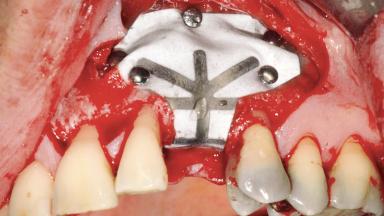

Guided Bone Regeneration (GBR) with a Particulated Autologous Graft and a ePTFE-Reinforced Membrane for Vertical Augmentation of a Single-Tooth Edentulous Space in the Esthetic Zone

A 47-year-old Caucasian woman with a single-tooth edentulous space at the site of the left maxillary canine was referred for treatment. She had undergone traumatic extraction of this impacted canine several months before referral. Her chief complaint was the dissatisfying appearance of her smile. The patient desired a stable and esthetic rehabilitation of the site. Her dental history showed no evidence of periodontal disease or bruxism. She had no systemic diseases, was not taking any medications, and did not smoke. The extraoral examination revealed a high lip line and an inadequate soft-tissue volume at the defective canine site. Large black triangles were visible between the canine and its adjacent teeth.

Bone Augmentation Staged|Vertical

Augmentation Materials Autogenous chips|Membrane

Bone Volume Deficient vertically or deficient vertically AND horizontally